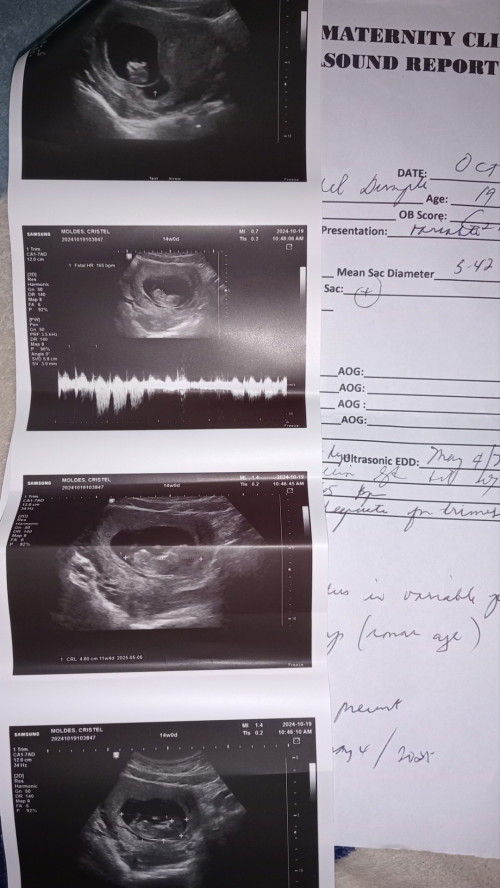

Good morning mamshies. FTM here with PCOS. More than 10 years din namin inantay ni hubby. Nagpatvs ako 2nd week ng Oct. Gestational sac pa lang. Pinabalik ako 2 weeks after. This week ako nakaschedule ulit ng tvs. May nga nireseta na sa unang consultation ko pa lang. Maselan daw kaya nakabed rest ako#firstimemom